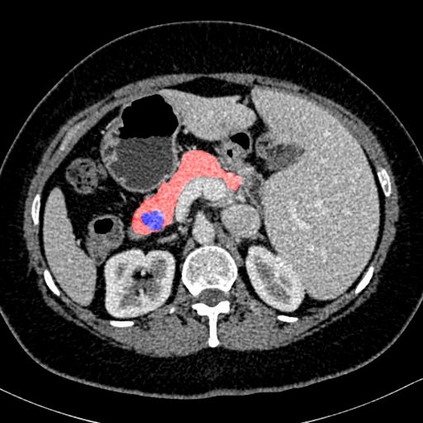

In this paper, we adopt 3D Convolutional Neural Networks to segment volumetric medical images. Although deep neural networks have been proven to be very effective on many 2D vision tasks, it is still challenging to apply them to 3D tasks due to the limited amount of annotated 3D data and limited computational resources. We propose a novel 3D-based coarse-to-fine framework to effectively and efficiently tackle these challenges. The proposed 3D-based framework outperforms the 2D counterpart to a large margin since it can leverage the rich spatial infor- mation along all three axes. We conduct experiments on two datasets which include healthy and pathological pancreases respectively, and achieve the current state-of-the-art in terms of Dice-S{\o}rensen Coefficient (DSC). On the NIH pancreas segmentation dataset, we outperform the previous best by an average of over 2%, and the worst case is improved by 7% to reach almost 70%, which indicates the reliability of our framework in clinical applications.